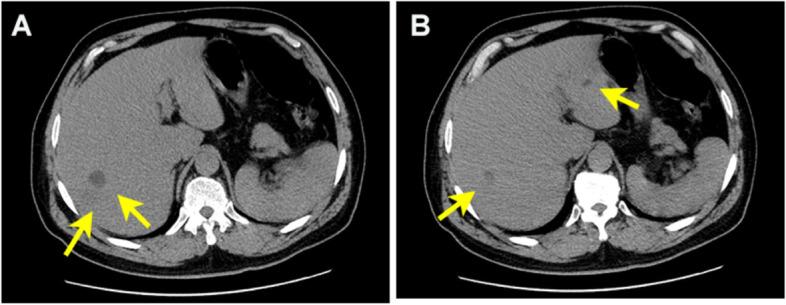

A 54-year-old male patient came to our department with a fever for 2 days and altered mental status for 1 day. Abdominal computed tomography (CT) and liver magnetic resonance imaging (MRI) revealed multiple liver abscesses. The blood culture was identified as Klebsiella pneumoniae sepsis. Head contrast-enhanced MRI and magnetic resonance venography (MRV) imaging showed multiple thrombus formation in the right transverse sinus and sigmoid sinus. The patient's infection and thrombosis were controlled within one week of multidisciplinary comprehensive treatment such as antibiotic and antithrombotic therapy, and a good clinical recovery during the 1-month follow-up.

一名 54 岁男性患者因发热 2 天伴精神状态改变 1 天来我院就诊。腹部 CT 和肝脏 MRI 显示多发肝脓肿。血培养鉴定为肺炎克雷伯菌败血症。头部增强 MRI 和磁共振静脉造影(MRV)成像显示右侧横窦和乙状窦多发血栓形成。经过多学科综合治疗(如抗生素和抗血栓治疗)一周后,患者的感染和血栓得到控制,在 1 个月的随访期间临床恢复良好。